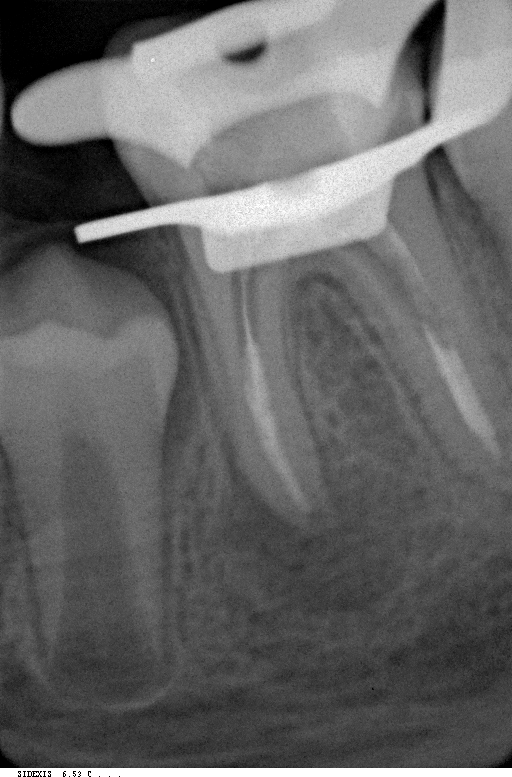

Эндодонтия

Эндодонтическое лечение зубов под микроскопом